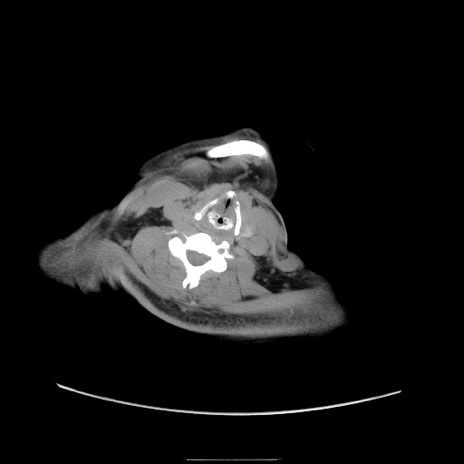

症例22(横断像)

【症例】50歳代男性

【主訴】腹痛

【現病歴】AVMからの被殻出血のため回復期リハ病棟入院中。 本日午後3時頃急に下腹部痛が出現した。

【既往歴】AVM、被殻出血、虫垂炎、高血圧

【身体所見】意識晴明、左半身不全麻痺、会話の理解は良好、36.5°C、腹部:膨隆、全体に板状硬、下腹部正中に圧痛点あり、反跳痛-、筋性防御不明、右下腹部にope scar

【データ】WBC 9400、CRP 0.06